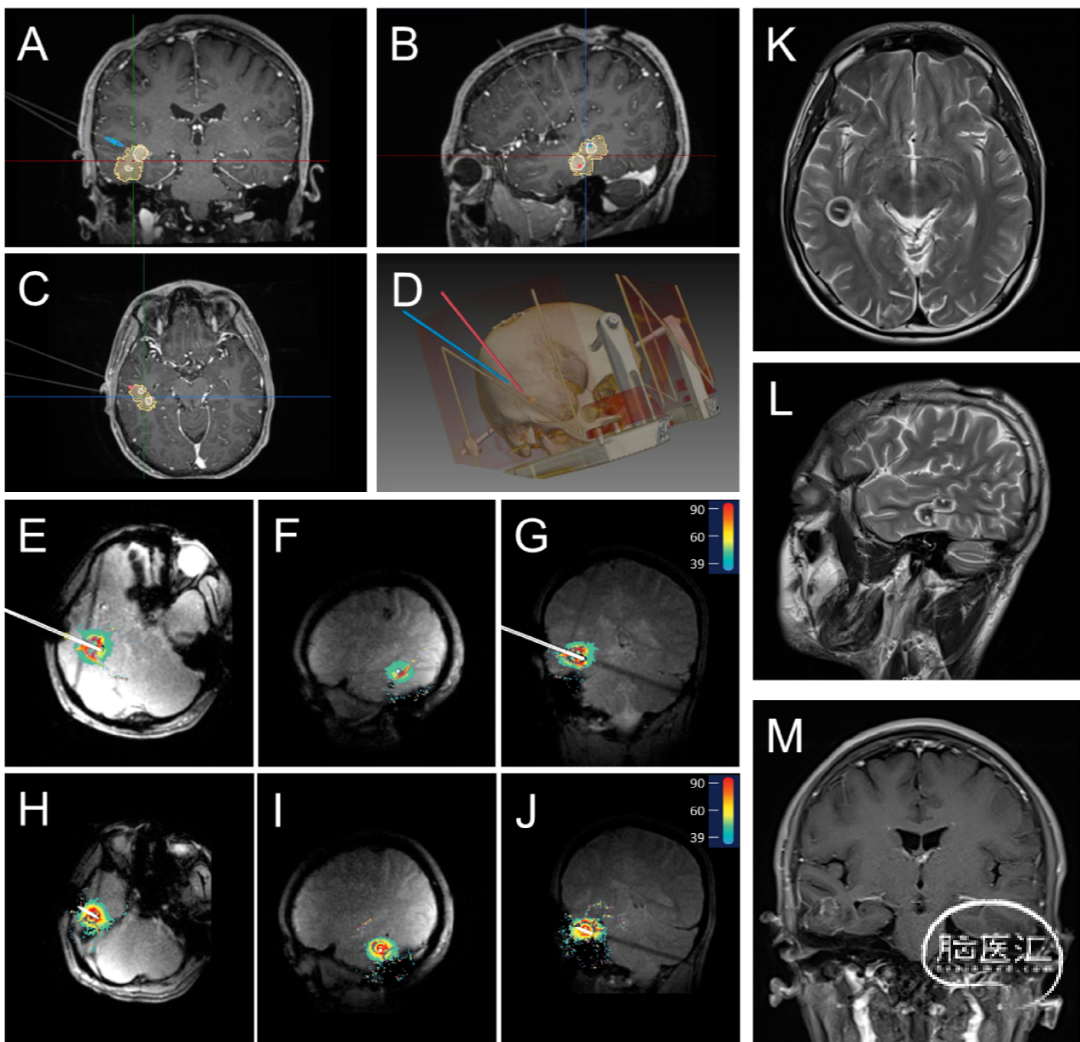

术前使用立体定向手术计划软件(V1.0,佳量医疗科技有限公司,中国,杭州)计划靶点位置、大小和光纤轨迹,以产生临时靶点坐标。所有手术均在全麻下完成,运动Leksell立体定向框架或神经外科机器人进行立体定向手术。切开皮肤,用电钻钻取颅骨,然后电凝烧灼硬脑膜。固定颅骨骨锚,计算电极插入深度,硬质清洁棒破入脑内建立通道后,依次插入并固定两根激光光纤。患者术中磁共振线圈固定后,移入术中磁共振室,接受初始术中MRI(Discovery MR750w 3.0T,GE Medical System,US)扫描,以检查光纤的准确定位,相关操作步骤如图1所示。

所有消融均使用LaserRO™MRI引导激光消融系统(Genlight Inc,Hangzhou,Zhejiang,China)进行,包括术前计划和术中消融。术前计划包括将消融手术计划(目标和轨迹信息、消融参数计划)输入手术平台。术中手术基于消融平台、光纤套件和手术工具,使用来自MR设备的实时图像进行治疗。系统通过冷却模块向光纤探头输出冷却水。在整个治疗过程中,消融平台采集实时图像,检测靶区及其周围组织的温度,确保安全有效的消融,相关消融过程如图2–4所示。

LaserRO™系统在设计中具有独特的技术规格。在主要性能方面,它采用了980nm和1064nm双波长光源,最大激光功率可达15W。探头有两种外径:1.55mm和2.3mm,三种不同的扩散尖端长度:4mm、10mm和15mm。冷却系统提供实时流量和残留物监测。插入式光纤探头兼容1.5T和3.0T MRI环境,MRI温度检测间隔为3.5秒,测温精度为±2°C。